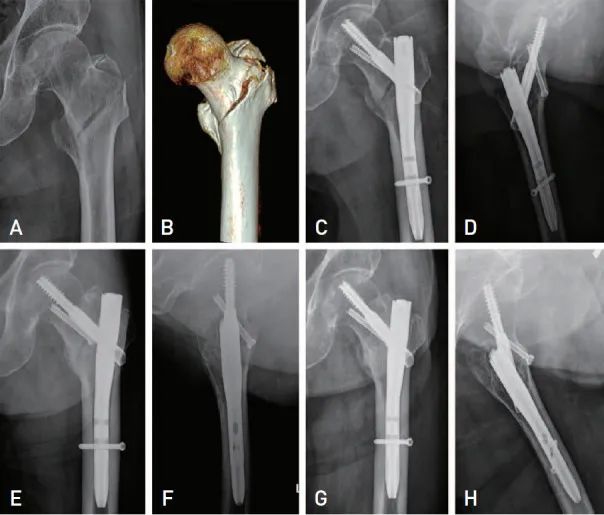

图2 91岁男性患者的术前和术后图像。(A, B)X 片和 3D 重建CT显示转子周围骨折在初始阶段为髓内定位的近端头颈骨折。( C, D ) 术后即刻AP和侧位片显示头髓钉和复位螺钉固定。( E, F ) AP 和侧位片显示术后 6 周骨折复位状态良好,骨折间隙早期骨痂形成。( G, H ) 术后 1 年末次随访时,AP 和侧位片证实骨折愈合。

该研究34名转子间骨折患者,使用当前的新型复位螺钉技术进行复位后,均成功实现骨折愈合,且拉力螺钉没有过度滑动(超过5mm视为过度滑动,可导致固定失败)。该研究平均滑动距离为2.1mm,低于之前使用股骨近端钉固定而无额外复位螺钉的研究。虽然近端骨折片和远端骨折片之间的微动对于股骨转子间骨折治疗很重要,但在该研究中,近30%的患者在术后六周内出现早期愈合组织形成。